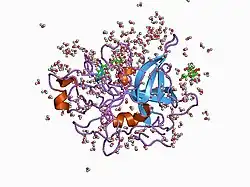

Urokinase is a 411-residue protein, consisting of three domains: the serine protease domain (consisting of residues 159–411), the kringle domain (consisting of residues 50-131), and the EGF-like domain (consisting of residues 1-49). The kringle domain and the serine protease domain are connected by an interdomain linker or connecting peptide (consisting of residues 132–158). Urokinase is synthesized as a zymogen form (prourokinase or single-chain urokinase), and is activated by proteolytic cleavage between Lys158 and Ile159. The two resulting chains are kept together by a disulfide bond between Cys148 and Cys279.[9]

In comparison to the mammalian system, zebrafish (Danio rerio) contains two orthologs of urokinase which have been characterised as zfuPA-a and zfuPA-b. zfuPA-a differs from the mammalian uPA by lacking an exon sequence encoding for the uPAR (urokinase receptor) binding domain; while the zfuPA-b lacks two cysteines of the epidermal growth factor-like domain. zfuPA-b also has no binding activity in fish white blood cells or fish cell lines. The uPAR binding in mammalian system is essential for the activity of urokinase and uPAR as it also functions as an adhesion receptor due to its affinity to vitronectin, integrins and other proteases like PAI-1. The lack of the uPAR binding region in zebrafish uPA, suggests that zebrafish uPA functions without uPAR binding.[10]

Interaction partners

The most important inhibitors of urokinase are the serpins plasminogen activator inhibitor-1 (PAI-1) and plasminogen activator inhibitor-2 (PAI-2), which inhibit the protease activity irreversibly. In the extracellular matrix, urokinase is tethered to the cell membrane by its interaction to the urokinase receptor.